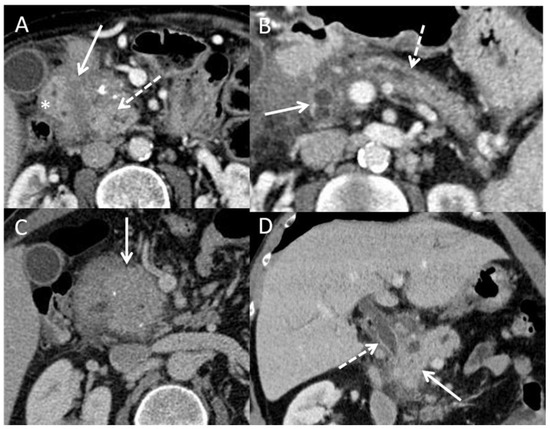

| Signs Evocative of Benign Disease | Signs Evocative of Malignant Disease | |

|---|---|---|

| Parenchymal signs | Pseudotumorous CP and IPMN:

|

Paraduodenal pancreatitis:

| ||

AIP:

| Duct signs | Obstructive CP and IPMN:

| Vessels signs | Pseudotumorous CP:

| Other signs | AIP: